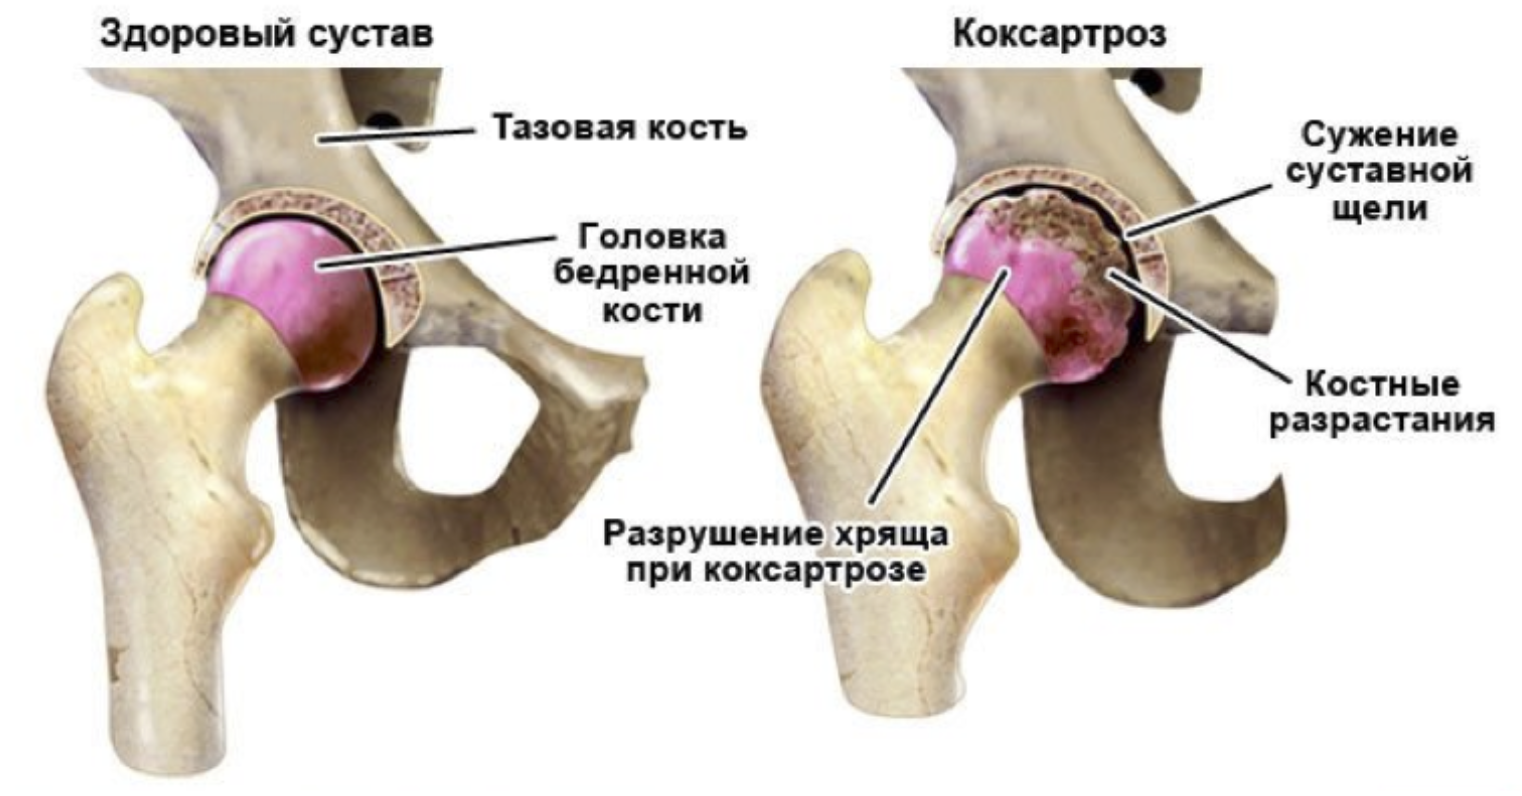

Синовит тазобедренного сустава – это воспаление синовиальной оболочки, которое может привести к болям и ограничению подвижности. Важно своевременно обращаться к специалисту и соблюдать комплексное лечение, включающее как медикаментозную терапию, так и рекомендации по физиотерапии и образу жизни. В этой статье вы найдете полезные советы по облегчению симптомов и ускорению выздоровления.

Синовит тазобедренного сустава

Синовит тазобедренного сустава